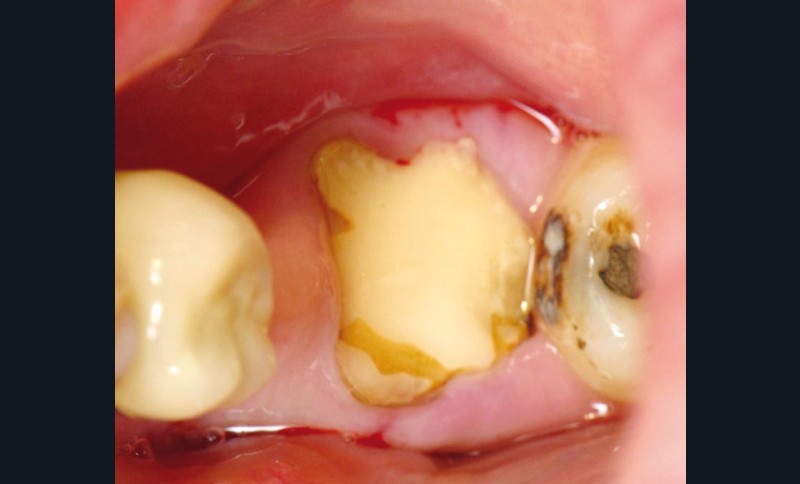

Pour avulser une molaire qui ne répond plus aux traitements conservateurs (fig. 1) et positionner un implant dans le même temps, nous devons résoudre les deux problématiques suivantes : extraire les racines en préservant le maximum de capital osseux et créer le lit implantaire sans détruire le septum inter-radiculaire.